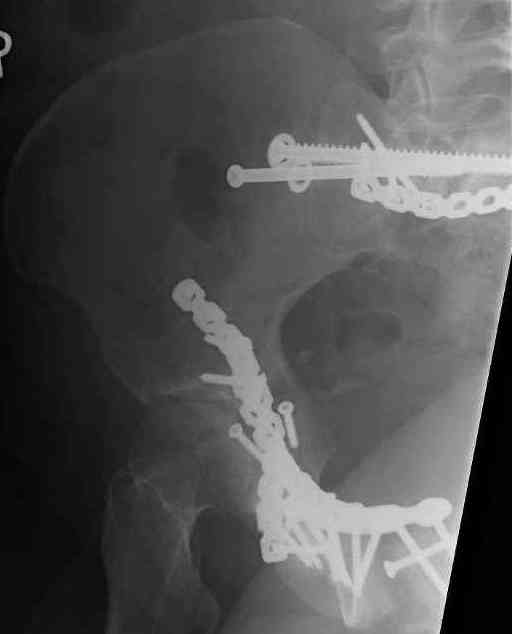

Looking for advice. This is a 48 yo non-smoking female s/p MCC 10 months ago. I do not have the initial injury films. She underwent ORIF as shown on attached file. She is having continued pain in low back/sacral region. Worse with sitting and prolonged walking. Has had pain since surgery. All of her wounds have healed uneventfully. Also has right hip pain laterally. No groin pain. Not aggravated with ROM of the hip. Infection work-up has been negative.

Any thoughts on the broken plate on the pelvic brim and the non-union on the anterior column. Doesn't seem like she's have pain from there.

Suggestions on treatment of sacral nonunion.

Maybe remove the disengaged iliosacral screw first to see if she improves?

I can't see the axial CT images well enough to detail the potential sacral issues....can you magnify them?